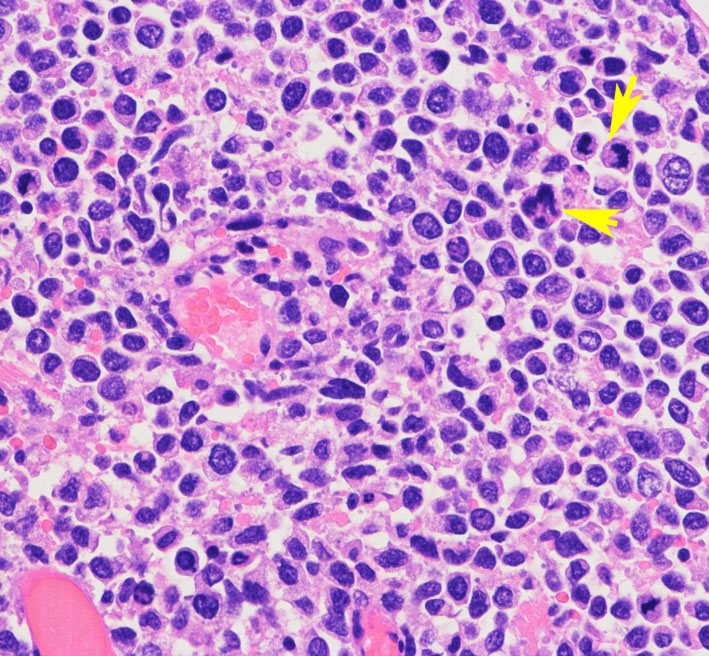

- 病理組織学的には,異型性の高いリンパ球の腫瘍細胞が,血管周囲に集まりさらに深く周囲の脳実質内に浸潤しています

円形から楕円形の核腫大を伴う異型細胞がびまん性に増殖しています。核は水泡状のものが目立ちます。黄色の矢印は核分裂像を示します。大細胞性リンパ腫 large B cell lymphoma の特徴的なHE染色像です。

Ki-67染色によるMIB-1染色率は80%を超え,細胞の分裂増殖が激しいことを示します。リンパ腫増殖はとても早く,1週間単位でMRI上の腫瘍増大が認められます。

CD20陽性のB細胞リンパ腫でした。